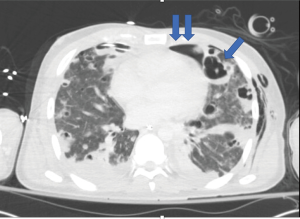

A 32-year-old male with a history of IV drug and tobacco use presented to the Emergency department with blunt chest trauma. He had pre-existing pulmonary septic emboli and developed severe acute respiratory distress syndrome (ARDS) requiring intubation and veno-venous extracorporeal membrane oxygenation (ECMO). While on ECMO he developed bilateral pneumothoraces from ruptured blebs complicated by bilateral bronchopleural fistulae. CT scan was obtained that revealed small volume pneumopericardium as well as bilateral pneumothoraces (Figure 1). Corresponding chest X-ray is seen in Figure 2. Several days after ECMO decannulation the patient developed acute agitation and hemodynamic instability. A chest X-ray was obtained that revealed air in the pericardial sac, cardiac compression, and mediastinal shift consistent with tension pneumopericardium (Figure 3). He was taken emergently to the operating room for pericardial window and drain placement. He was returned to the surgical ICU in critical, but improved, condition. Though rare, tension pneumopericardium should be on the differential diagnosis for shock in patients with blunt chest trauma, emphysematous lung disease, or bronchopleural fistula.